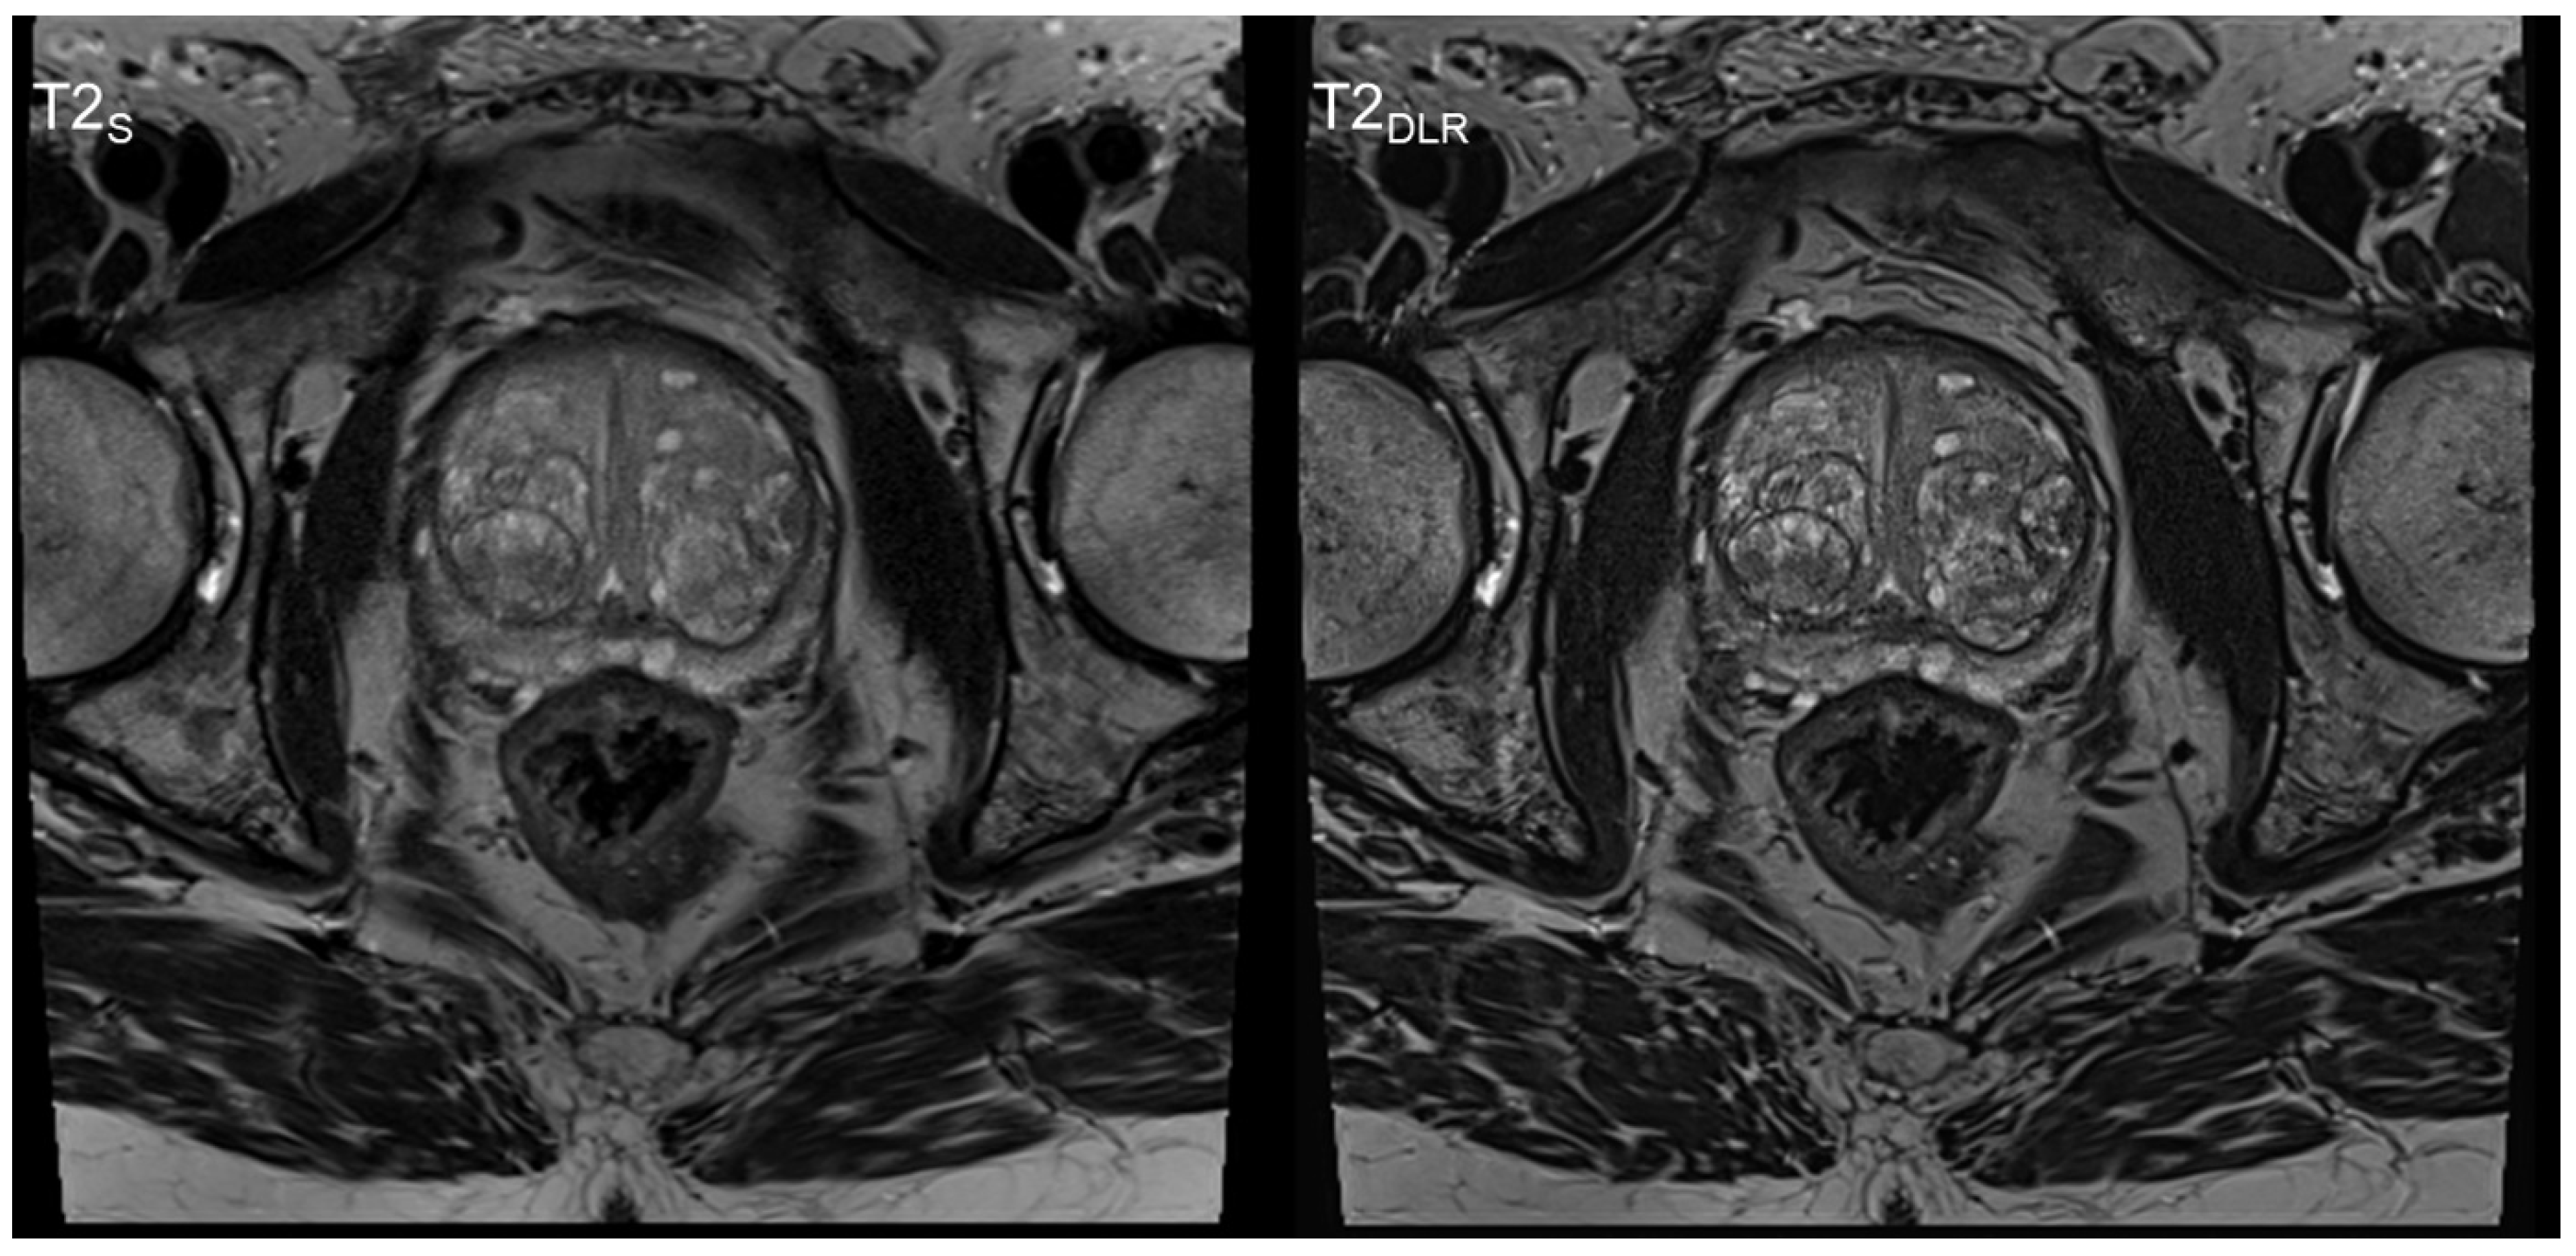

3. Results

3.1. Image Quality Analysis